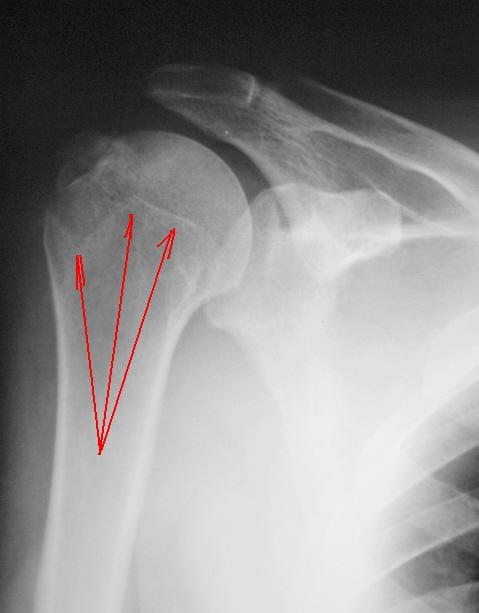

Насчет линейной тени (две медиальные стрелки) - думаю, не перелом это, закрытая зона роста.

Однозначно, линия, указанная стрелками, это бывшая ростковая зона.

Вот то, что отмечено желтыми стрелочками на последней серии снимков - и есть отрыв большого бугорка. Такой большооооой отрыв большоооооооого бугорка.